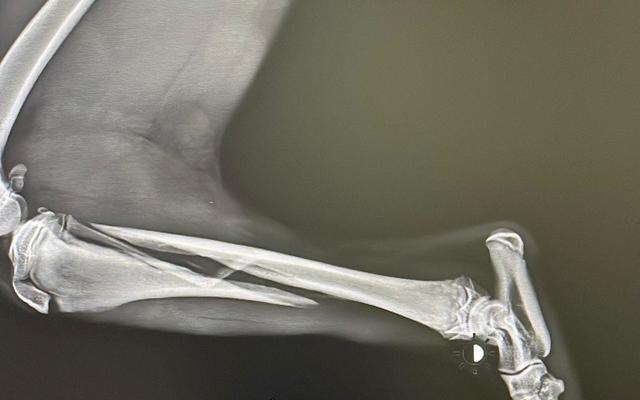

Esta perrita de tan solo 4-5 meses ya sabe bien lo que es el dolor.

Hace poco más de dos semanas os pedíamos ayuda, había que operarla de una fractura de tibia y necesitábamos una casa donde pudiera recuperarse.